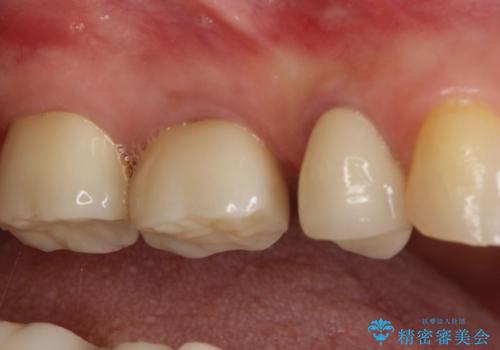

歯間空隙は、患者様と相談した清掃性を考慮し、結果的に残すこととなりました。